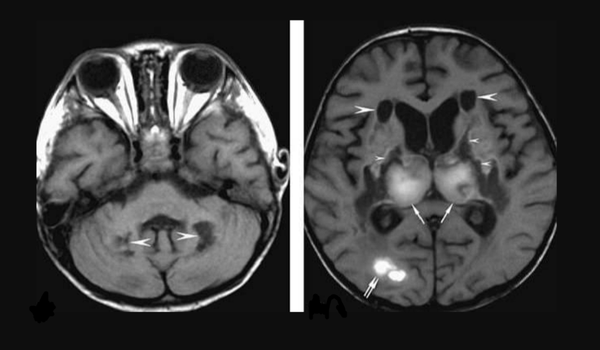

当时,医生也进行了CoViD-19测试,结果呈阳性。但病人身上出现的是新冠病毒疫情下的非典型症状,于是决定对其进行CT检查。扫描显示,病人大脑中负责记忆和传递信号的部分受损。结果,医生确诊,病人患上了急性坏死性脑病(acute necrotizing encephalopathy,ANE)。这是一种罕见的、严重的、经常会致命的疾病,在发生病毒性感染时就会发生。医生们都认为,罪魁祸首就是CoViD-19病毒。